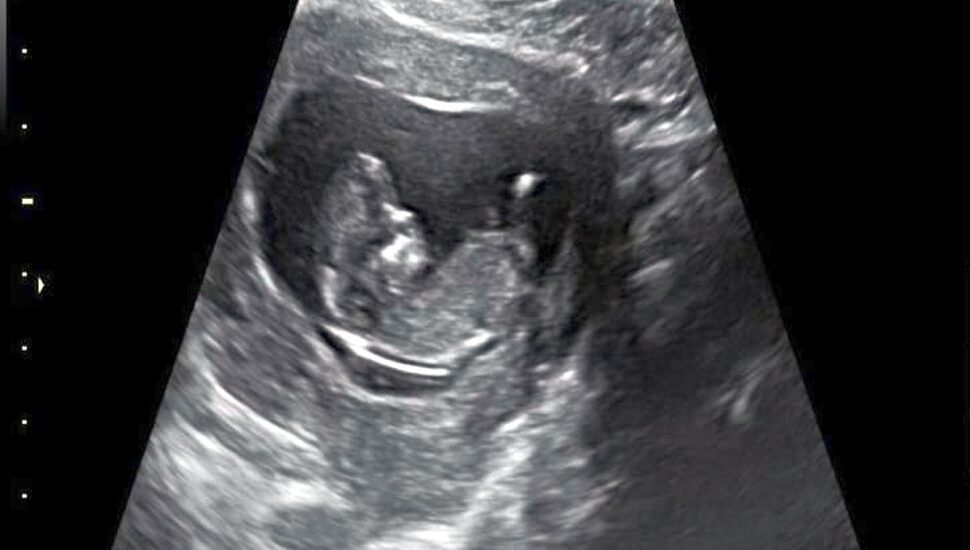

É doído, mas precisamos falar de perdas gestacionais e abortos. Foto: Arquivo Pessoal

Mas como somos um casal de pessoas teimosas, nosso filho não poderia ser muito diferente, já que o “fruto não cai muito longe do pé”, não é mesmo?! Inacreditavelmente quinze dias depois, engravidamos novamente. Dessa vez foi tudo diferente. O piazinho é teimoso e quer mesmo fazer parte da nossa família. Como um pequeno milagre, ele é perfeito e tudo está correndo bem desde os primeiros momentos.

E foi assim que engravidamos, “desengravidamos”, engravidamos novamente, “desengravidamos” mais uma vez e estamos aqui hoje com uma pancinha enorme e linda, que chuta e tem um bebê perfeito dentro.

É nosso final feliz, cheio de pequenos desvios e nem sempre tão agradável assim. Sinto medo todos os dias, e todas as pequenas dores e sintomas novos me assustam um pouco. Nossa obstetra um dia ainda vai me bloquear no WhatsApp. Sempre fico ansiosa antes dos exames, mas quero fazer o melhor em tudo para garantir que esse bebê venha pra casa com a gente daqui alguns meses.